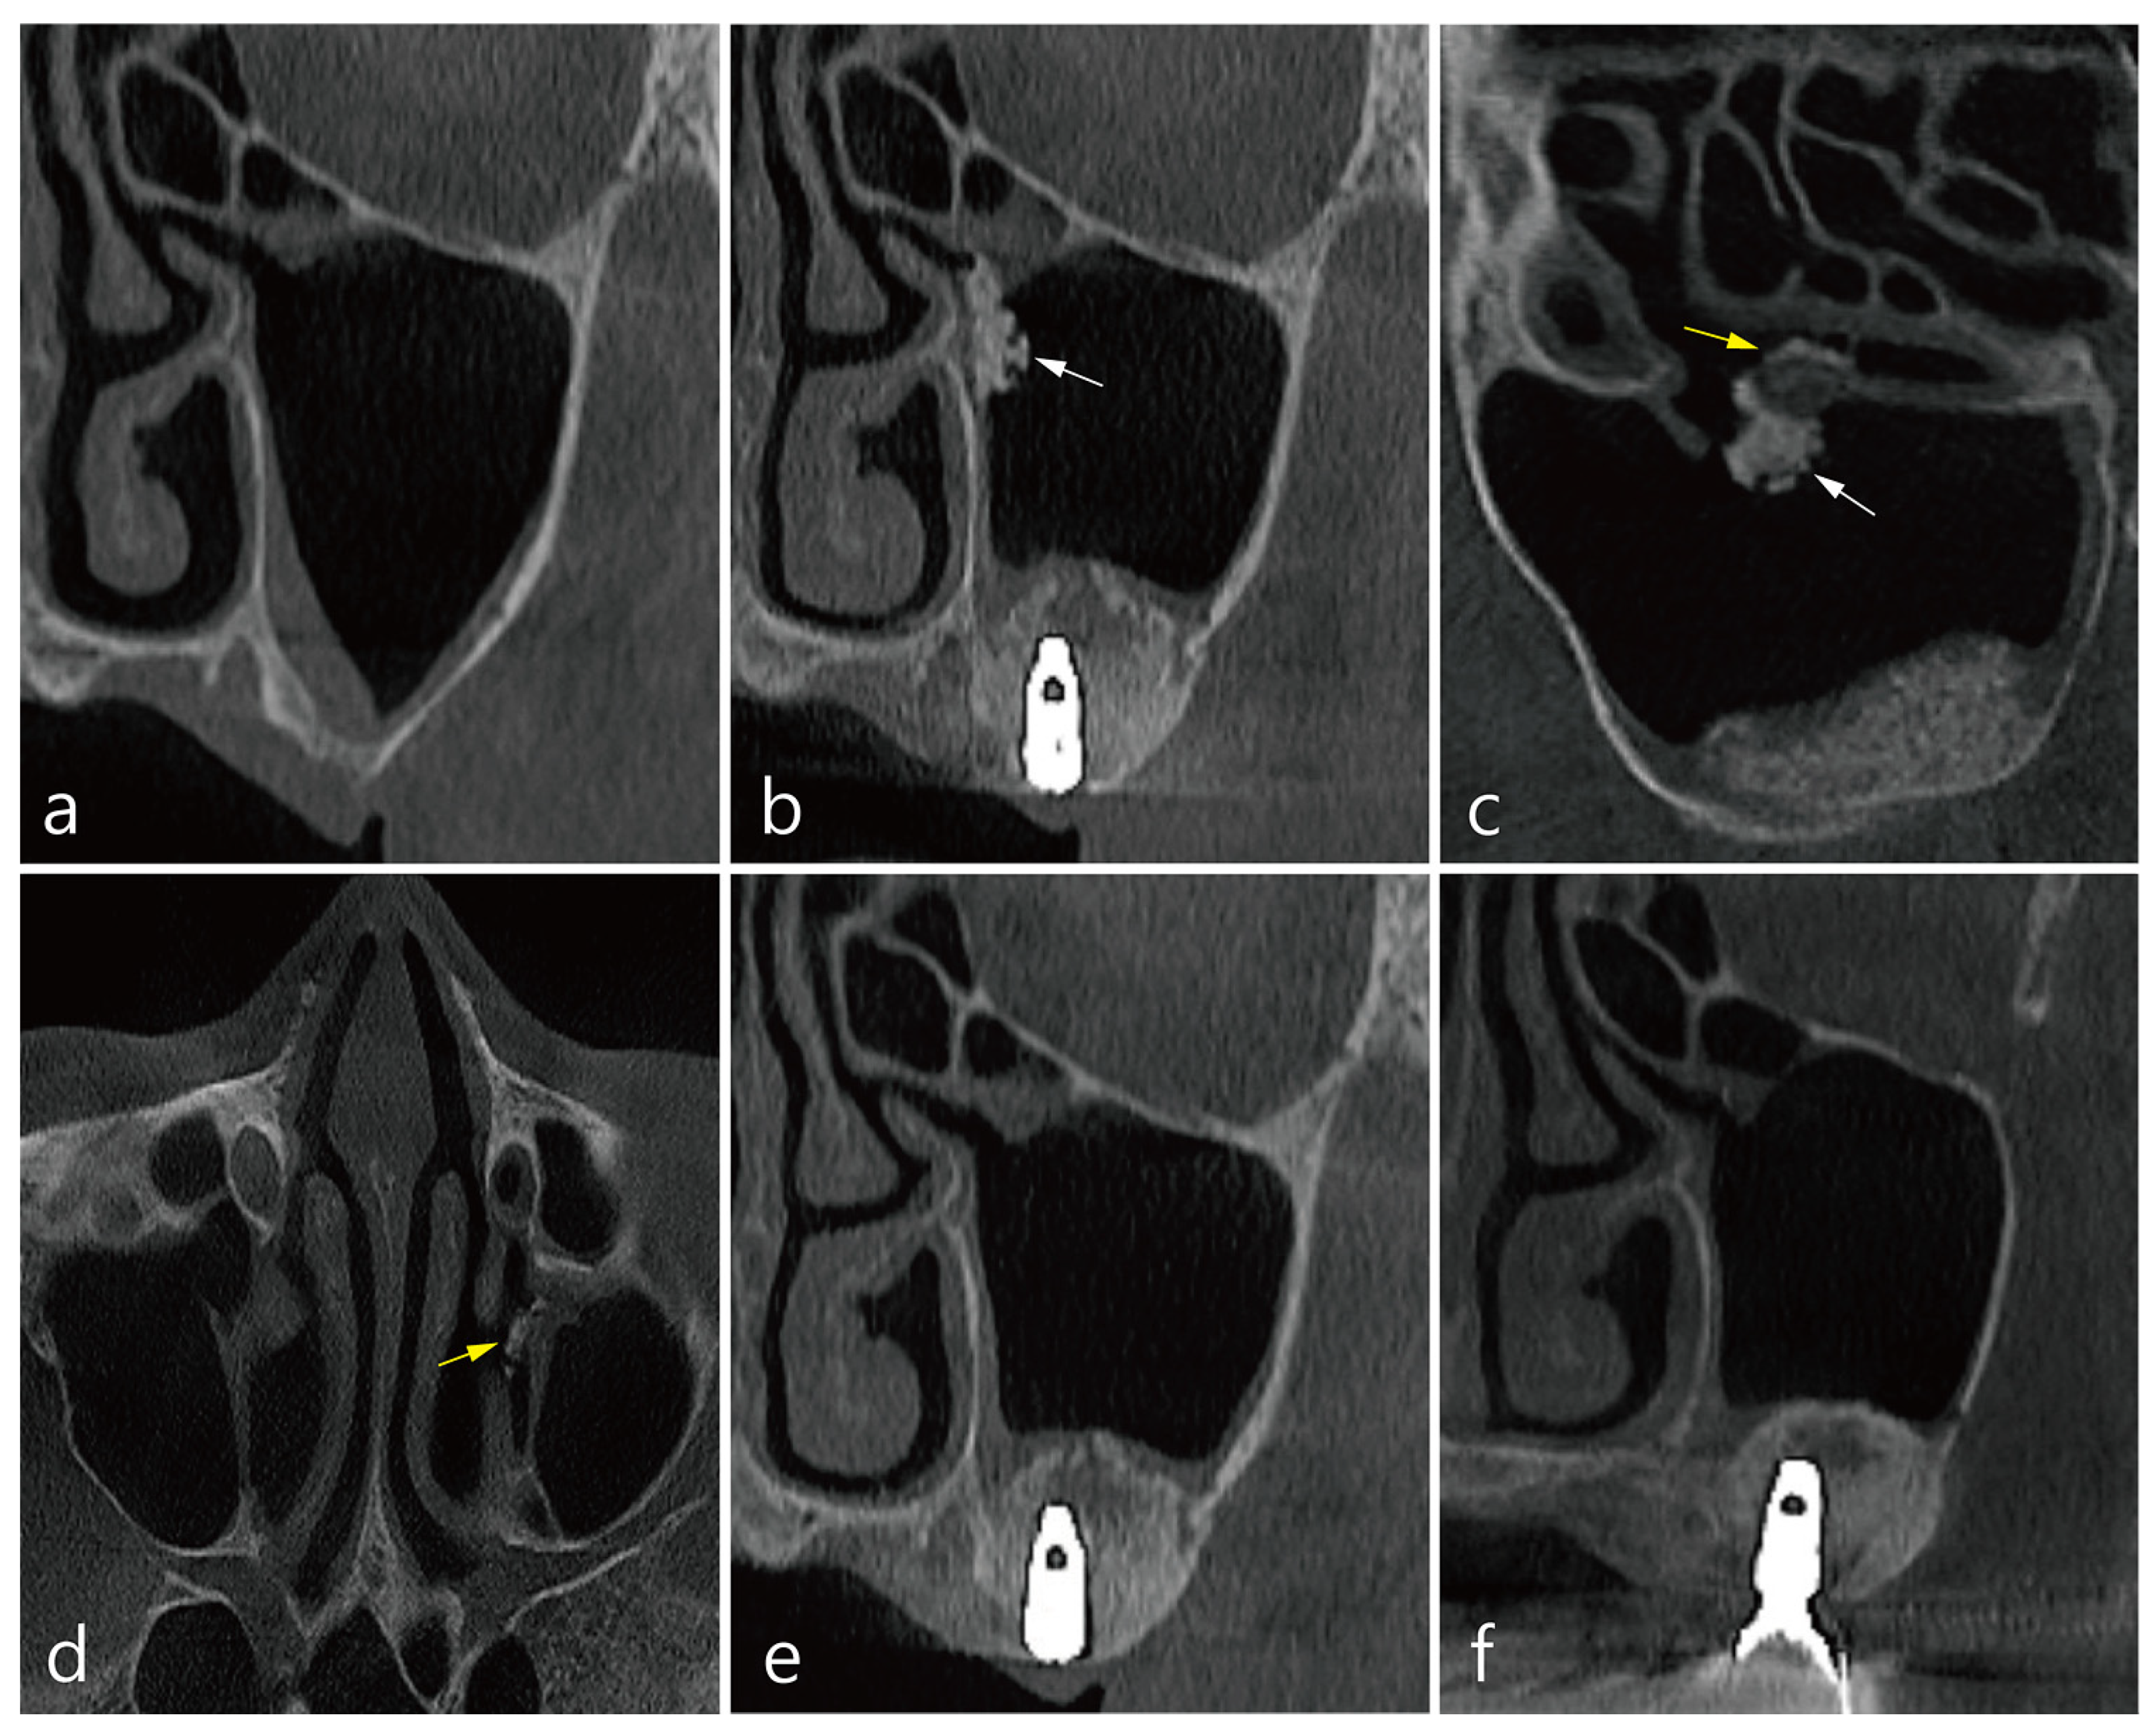

3. Case 1